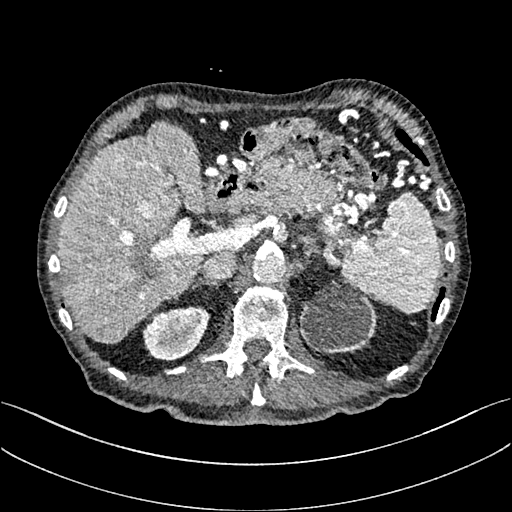

To demonstrate the effectiveness of the proposed network, we perform the qualitative comparisons over three representative abdominal images presented in Figs. 3, 5 and 7. For better evaluations of the image quality with different denoising models, zoomed regions-of-interest (ROIs) are marked by red rectangles and shown in Figs. 4, 6 and 8 respectively. Note that all results from different denoising models focus on two aspects: content restoration and noise-reduction. All CT images in axial view are displayed in the angiography window [-160, 240]HU.

The real NDCT images and corresponding LDCT images are presented in Figs. 3a and 3b. As observed, there are distinctions between ground truth (NDCT) images and LDCT images. Figs. 3a and 7a show the lesions/metastasis. Fig. 5a presents focal fatty sparing/focal fat. In Figs. 4a, 6a and 8a, these lesions can be clearly observed in NDCT images; in contrast, from Figs. 4b, 6b, and 8b, it can be seen that the original LDCT image is noisy, and lacks structural features for task-based clinical diagnosis. All adopted denoising models suppress noise to some extent.

To evaluate the effectiveness of our proposed objective function, we compare our method with existing WGAN-based networks, including WGAN and WGAN-VGG. Considering the importance of clinical image quality and specific structural features for medical diagnosis, we adopted the adversarial learning method [41, 42] in our experiments because WGAN could help to capture more structural information. Nevertheless, based on our prior experience, utilizing WGAN alone may yield stronger noise than other selected approaches, because it only maps the data distribution from LDCT to NDCT without consideration of local voxel intensity and structural correlations. The observations demonstrate that the noise texture is coarse in the images, as shown in Fig. 4g and Fig. 8g, which support our intuition.

Indeed, the images of WGAN-VGG[37], as shown in Fig. 3j, exhibit better visual quality with respect to more details and share structural details similar to NDCT images according to human perceptual evaluations. However, Figs. 4j (marked by the red circle) and 6j (marked by the green circle) suggest that it may severely distort the original structural information. A possible reason is that the VGG network [47] is a pre-trained deep CNN network based on natural images, and the structural information and contents of natural images are different from medical images.

Compared with WGAN and WGAN-VGG, our proposed SMGAN-3D, as shown in Figs. 4l (marked by the red circle) and 6l (marked by the green circle), can more clearly visualize the metastasis and better preserve of the portal vein.

In Figs. 7 and 8, it can be found that the SMGAN-based methods can achieve better anatomical feature preservations and visual quality than other state-of-the-art methods.

The experimental results demonstrate that our proposed objective function is essential to capture more accurate anatomical details.

To validate the robustness of DL-based methods, we compared our method with the image space denoising method. Figs. 4h and 6h show that BM3D blurs the low-contrast lesion marked by the red circle and smooths specific features marked by the blue arrow. In contrast, SMGAN-3D exhibits better on the low-contrast lesion and yields sharper features as shown in Figs. 4l and 6l.

III-D4 Comparison with 2D-based SMGAN network

In order to evaluate the 3D structural information, we compared SMGAN-3D with SMGAN-2D. As shown in Fig. 4l, our proposed SMGAN-3D generated the results with better subtle details than SMGAN-2D and enjoys more similar statistical noise properties to the corresponding NDCT images. The reasons why SMGAN-3D outperforms SMGAN-2D are follows. First, SMGAN-3D incorporates 3D structural information to improve image quality. Second, SMGAN-2D takes input slice by slice, thus potentially leading to the loss of spatial correlation between adjacent slices.

Figs. 7 and 8 demonstrate that the SMGAN-3D can be used to provide improved anatomical feature preservation over other state-of-the-art methods.

In summary, we compared our proposed methods with existing methods, and it can be clearly observed that SMGAN-3D achieves robust performance in noise suppression, artifact removal, and texture preservation. Note that we recommend the reader to see ROIs (in Fig. 4 and 6) or zoom in to better evaluate our results. To further validate the generalization ability of our proposed model, we conclude more details in Appendix A.